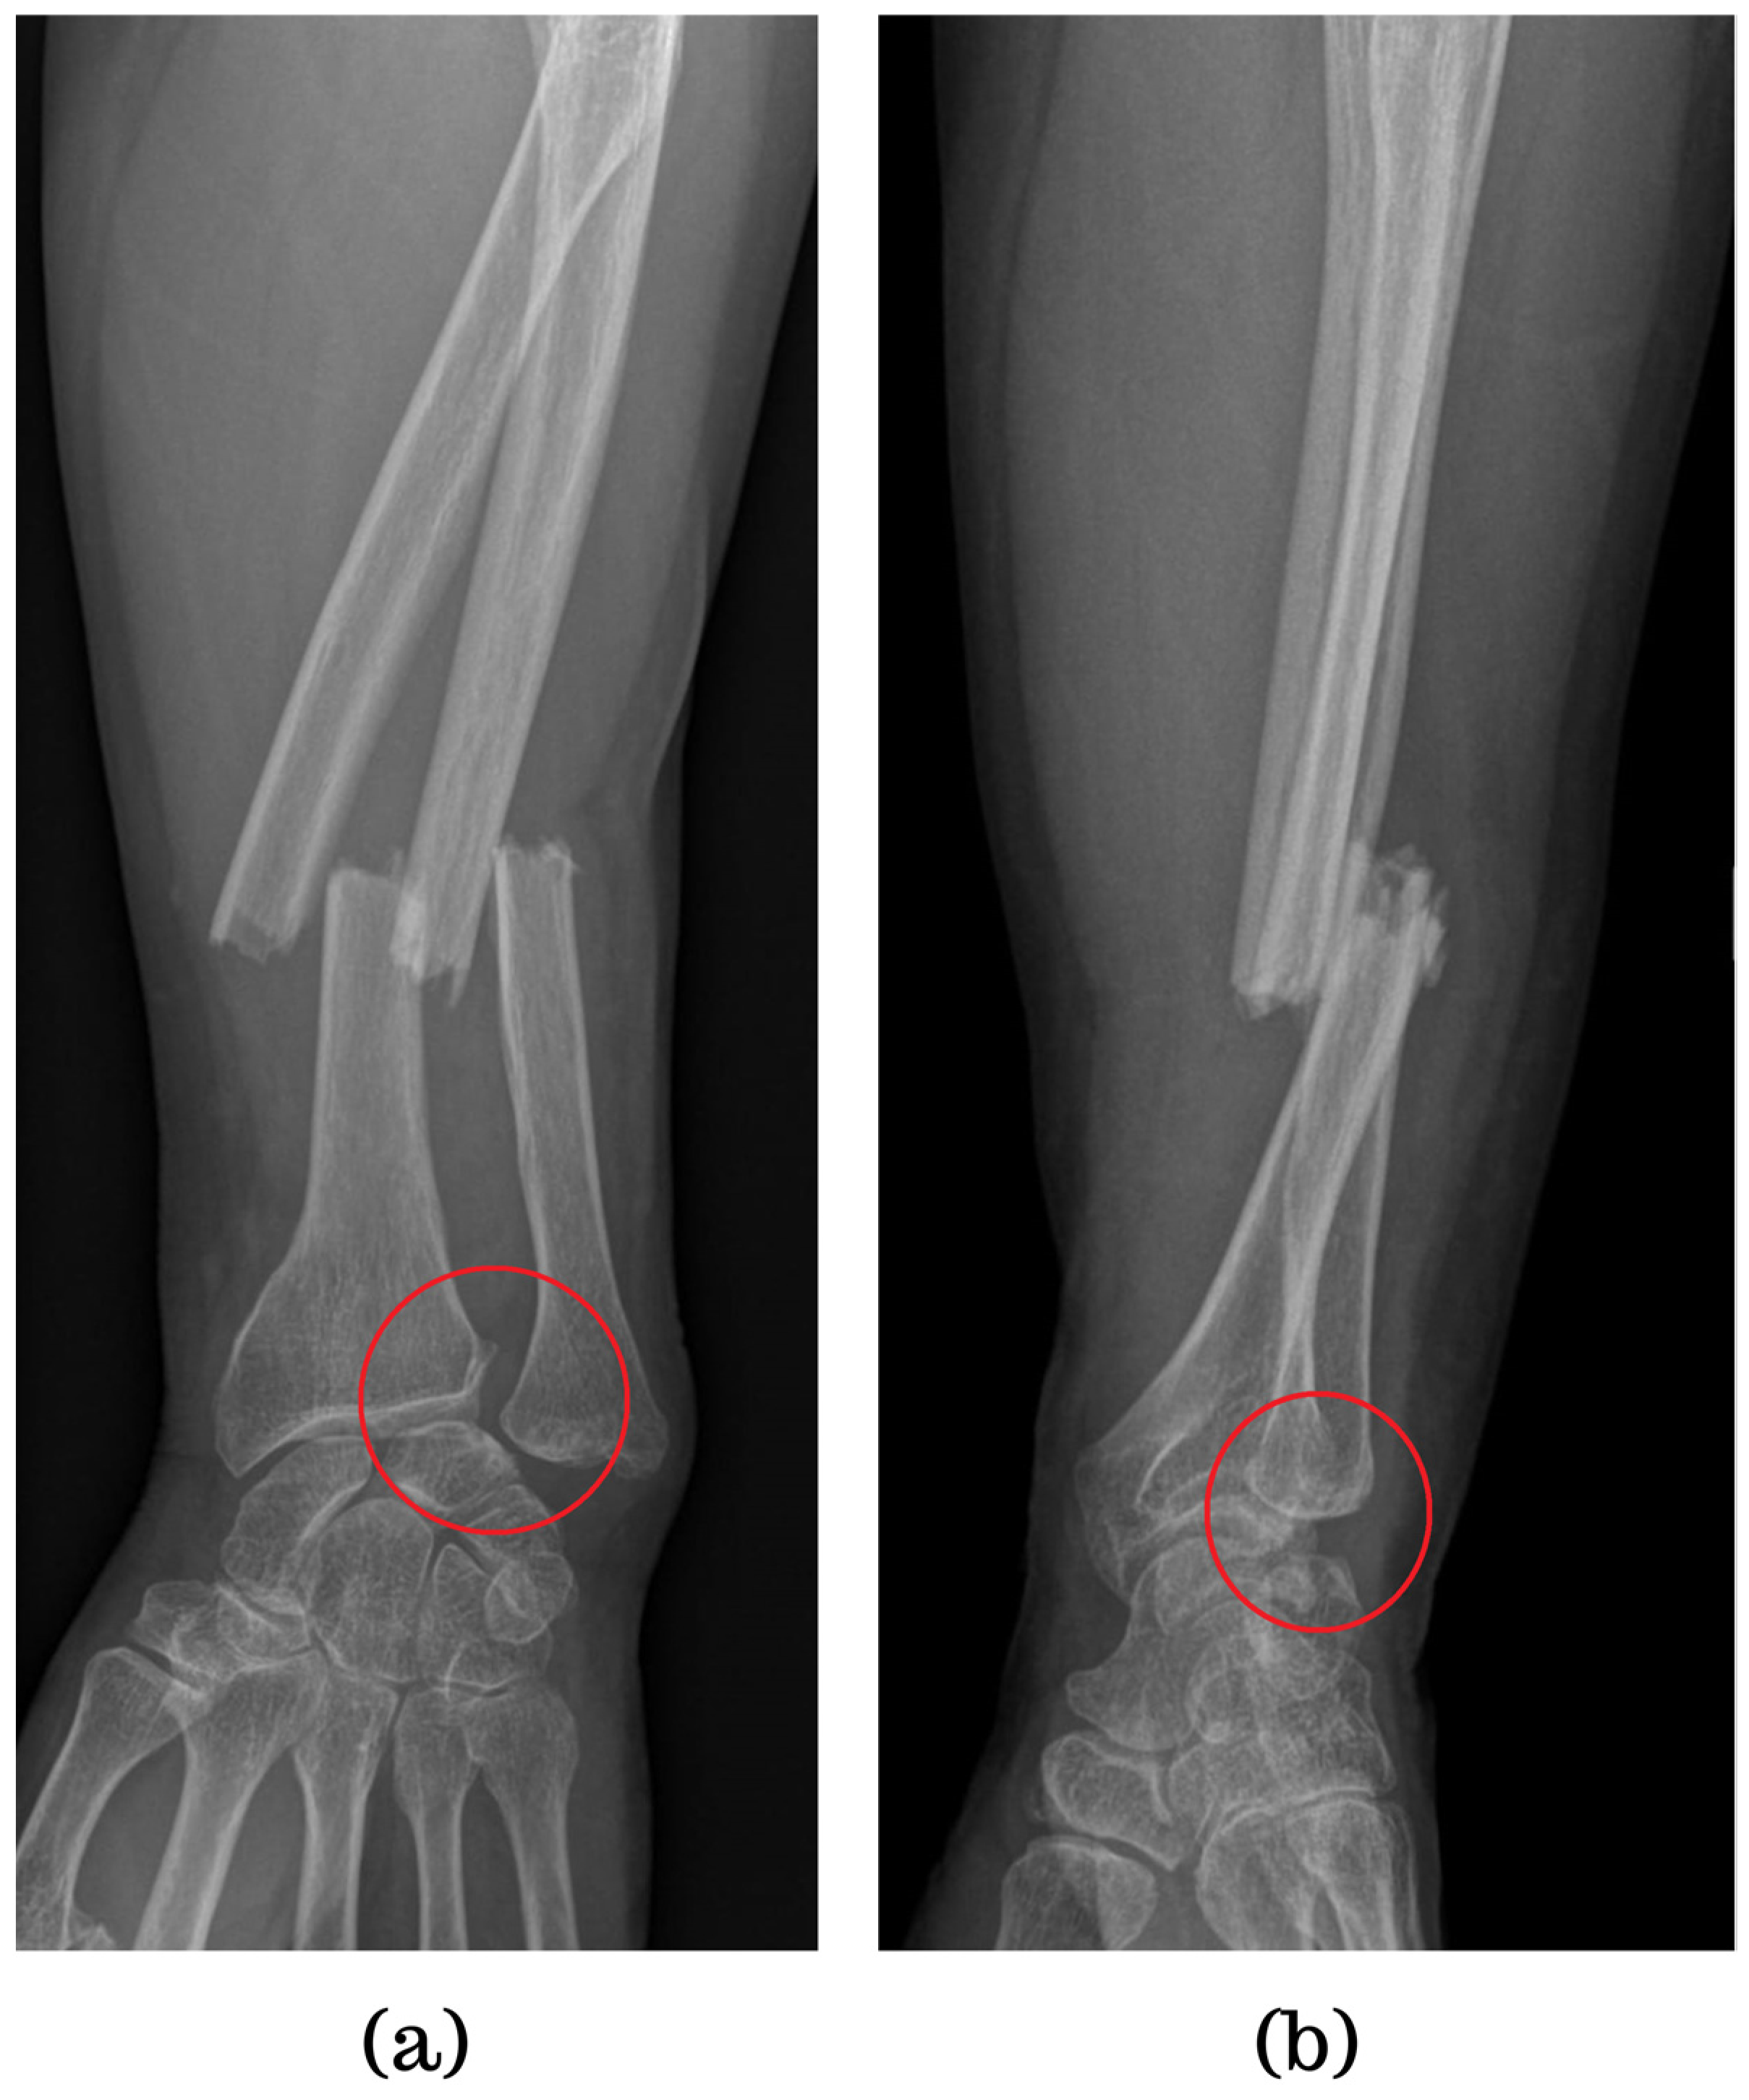

5.1. Conventional Radiography

| Galeazzi fractures | High-energy trauma | Clinical presentation: forearm swelling, deformity [60]. Imaging: X-rays, CT scans [7]. | Surgical intervention: ORIF, DRUJ stabilization [7,65,66], postoperative care and rehabilitation. Complications may include persistent pain, stiffness, instability [60]. | Comprises approximately 7% of all forearm fractures [61]. |